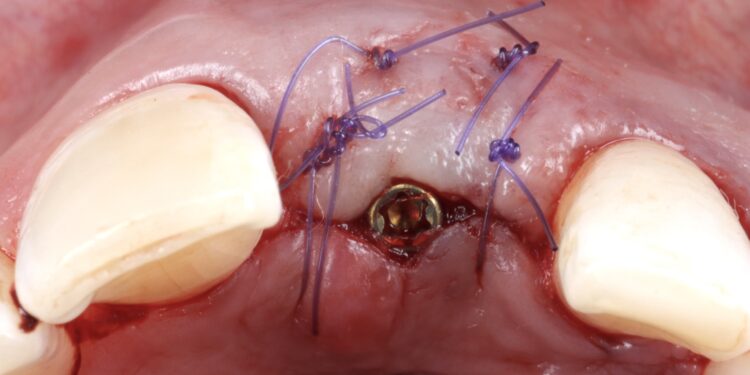

It was thus decided to carry out a ridge preservation graft to retain the existing alveolar ridge width and to use an open healing concept to encourage new soft tissue growth, increase keratinised tissue and avoid distortion of the mucogingival junction. This was carried out using the combination of MinerOss® Blend Allograft and a dense PTFE membrane.

Implant phase.